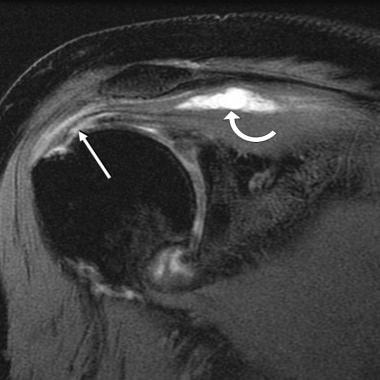

Figure 1: Rotator Cuff Tear This rotator cuff tear is seen in the The muscle is lit up in bright white and you can see a dark spot indicating the Figure 2: Partial Rupture This is a partial rupture of one of the rotator cuff The red arrow indicates the rupture Figure 3: Complete Rotator Cuff Tear